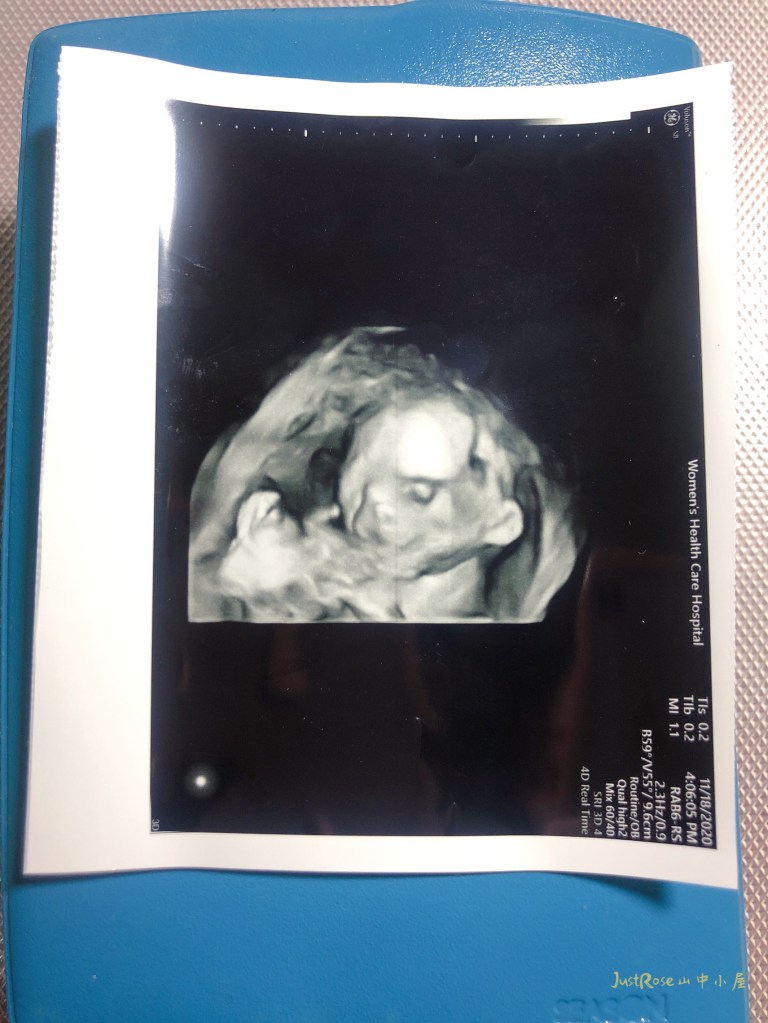

記得有一次,要確認性別時產檢的前一晚(我們在前幾週就已經大概知道性別),我也是跟他說明天醫生阿公會幫你照超音波,你的腳要開開一下,動一下,讓媽媽知道你的性別喔,隔天一照超音波馬上照到,之後每次都照到…溝通還真有效。他的活動力很好,除了有一次他應該在睡覺,其他的時候動作都很多,有時候瘋狂的揮手、伸腳,最近醫生開到3D,我們看到他的五官,他在微笑。(18週,在20週以上五官會更明顯)